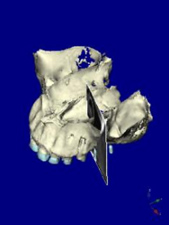

術前CT 2

第一大臼歯部

インプラントをシミュレーション